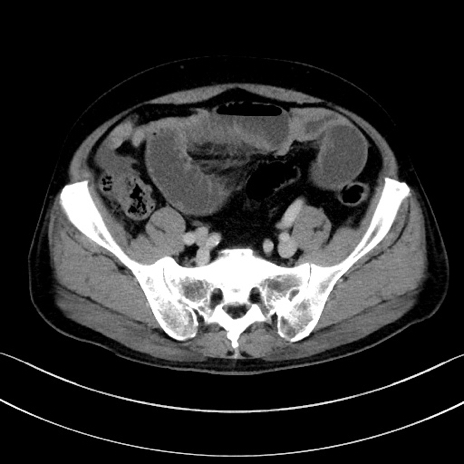

症例15(横断像)

【症例】70歳代男性

【主訴】腹痛

【現病歴】今朝から腹痛あり。全体的に痛い。特に左上の方。排ガスが今日はない。冷や汗が出る。

【既往歴】直腸癌術後

【身体所見】左側腹部〜上腹部に圧痛あり。腹膜刺激症状明らかなではない。軽度反跳痛。左下腹部に術後瘢痕あり。

【データ】WBC 7700、CRP 0.02